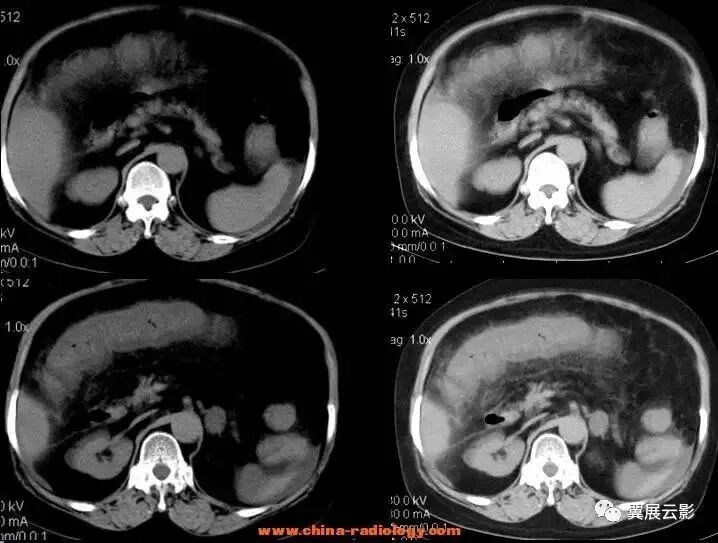

(该图来自《CT泪滴状肠系膜上静脉征评价胰头癌不可切除性的意义》一文, 中国医学影像技术2001年第17卷第2期)

图1 动态增强CT 示胰头部肿块紧邻 SMV、SMA,周围正常脂肪间隙消失,SMV受压呈泪滴状。

图2 螺旋增强CT 示胰钩突部一低密度肿块,SMA包绕受侵,SMV受压呈线形改变

图3 动态增强CT 示胰头部一密度不均匀肿块,与 SMV脂肪间隙消失,SMV受压呈椭圆形改变。

图4 螺旋增强CT 示胰头部一密度不均匀肿块,与 SMV脂肪间隙模糊但仍存在,三角形的 SMV为容积效应所致。

24、泪滴状肠系膜上静脉征(肠系膜上静脉变形征)

在横断面腹部增强CT及MRI,正常圆形的肠系膜上静脉受肿瘤组织挤压而变成泪滴状、线状或椭圆形。

门静脉由脾静脉和肠系膜上静脉在胰头后方汇合而成,在CT横断面上,正常胰头或其钩突与肠系膜上静脉之间有脂肪组织相分隔。当发生胰头癌时,肿瘤可向周围侵犯,突破脂肪层并向周围血管浸润。当肠系膜上静脉受到癌组织直接浸润或受到周围被累及的纤维结缔组织牵拉时,正常肠系膜上静脉的圆形断面可变为泪滴状、线状或椭圆形,肿瘤与肠系膜上静脉间的脂肪间隙消失,此征象被称为泪滴状肠系膜上静脉征。该征象的出现是判断胰头癌不可切除的可靠指征。

一组对泪滴状肠系膜上静脉征的研究显示,在其分析的92例患者中,该征在预测胰头癌不可切除性方面显示出高度的特异性(98%),其阳性预测值为95%。而且,在其他手段认为是可以切除的胰头癌患者中,该征预测不可切除性的敏感性达76%。